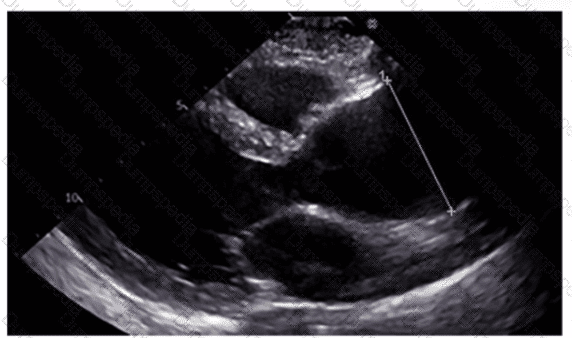

Which region of the aorta is being measured to assess the critical finding in this image?

Using your mouse, place the cursor on the appropriate region of the image and then left click the mouse button to indicate your selection.